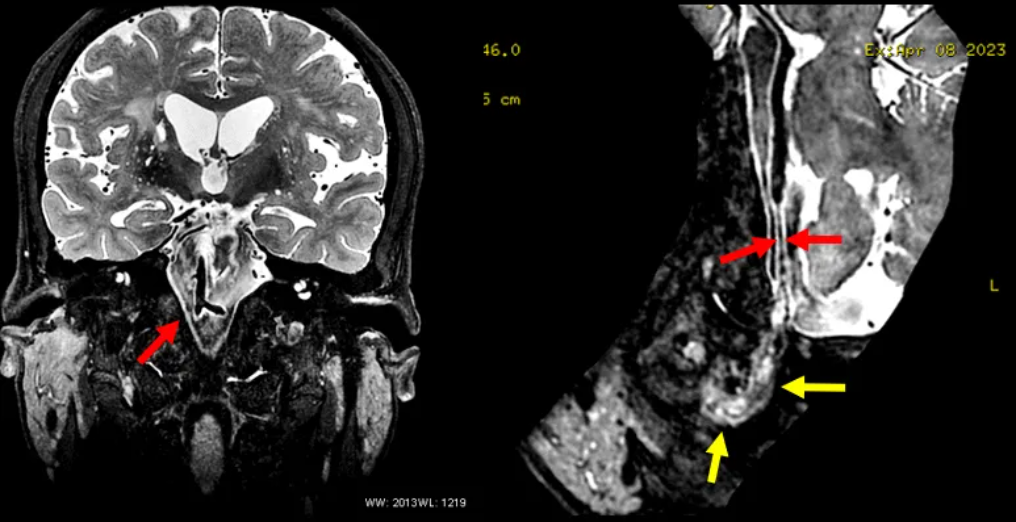

六、MR血管壁成像

结合高分辨磁共振图像,可以看到椎动脉残端在闭塞的椎动脉入颅段是有延续的,拥有完整的动脉壁,同时闭塞血管内血栓致密,这种情况下椎动脉残端出现破裂出血的风险大大降低,暂时不需要外科干预,长期风险也缺乏研究证据,出院后长期随访残端的变化。